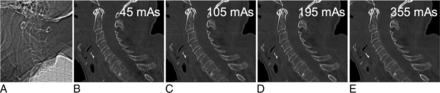

Lateral topogram (A) of this cadaveric specimen reveals shoulder height at the C5 level. Sagittal reformatted CT images (B–E; window level/width, 600/2000) of the cervical spine at 45, 105, 195, and 355 mAs reconstructed with sonogram-affirmed iterative reconstruction (strength level, 3) using bone convolution kernels show a decreasing image noise with increasing tube currents, but still sufficient image quality at 105 mAs compared with 355 mAs.